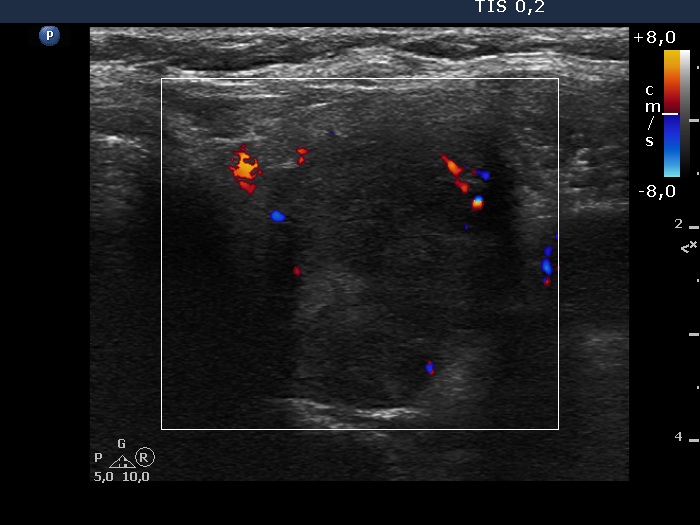

Follow-up examination six years after the first visit (ultrasonographic picture 10)

Upper part of the left lobe, transverse scan, color Doppler mode. The nodule presents signs of intranodular vascularization.